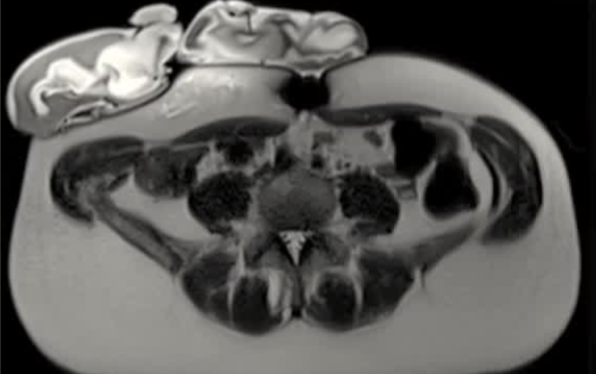

| 腹壁下病变 | MRI引导下 冷冻消融。装有热水的手套在皮肤表面保护皮肤 |

通常需要三根布针

隔离和布针

保护措施:几乎所有干预都需要辅助保护措施,其中水分离术(13/16,81.3%)和水分离术与温盐水填充手套的皮肤保护结合(9/16,56.3%)是最常见的保护措施。

采用冷冻循环(功率与持续时间)